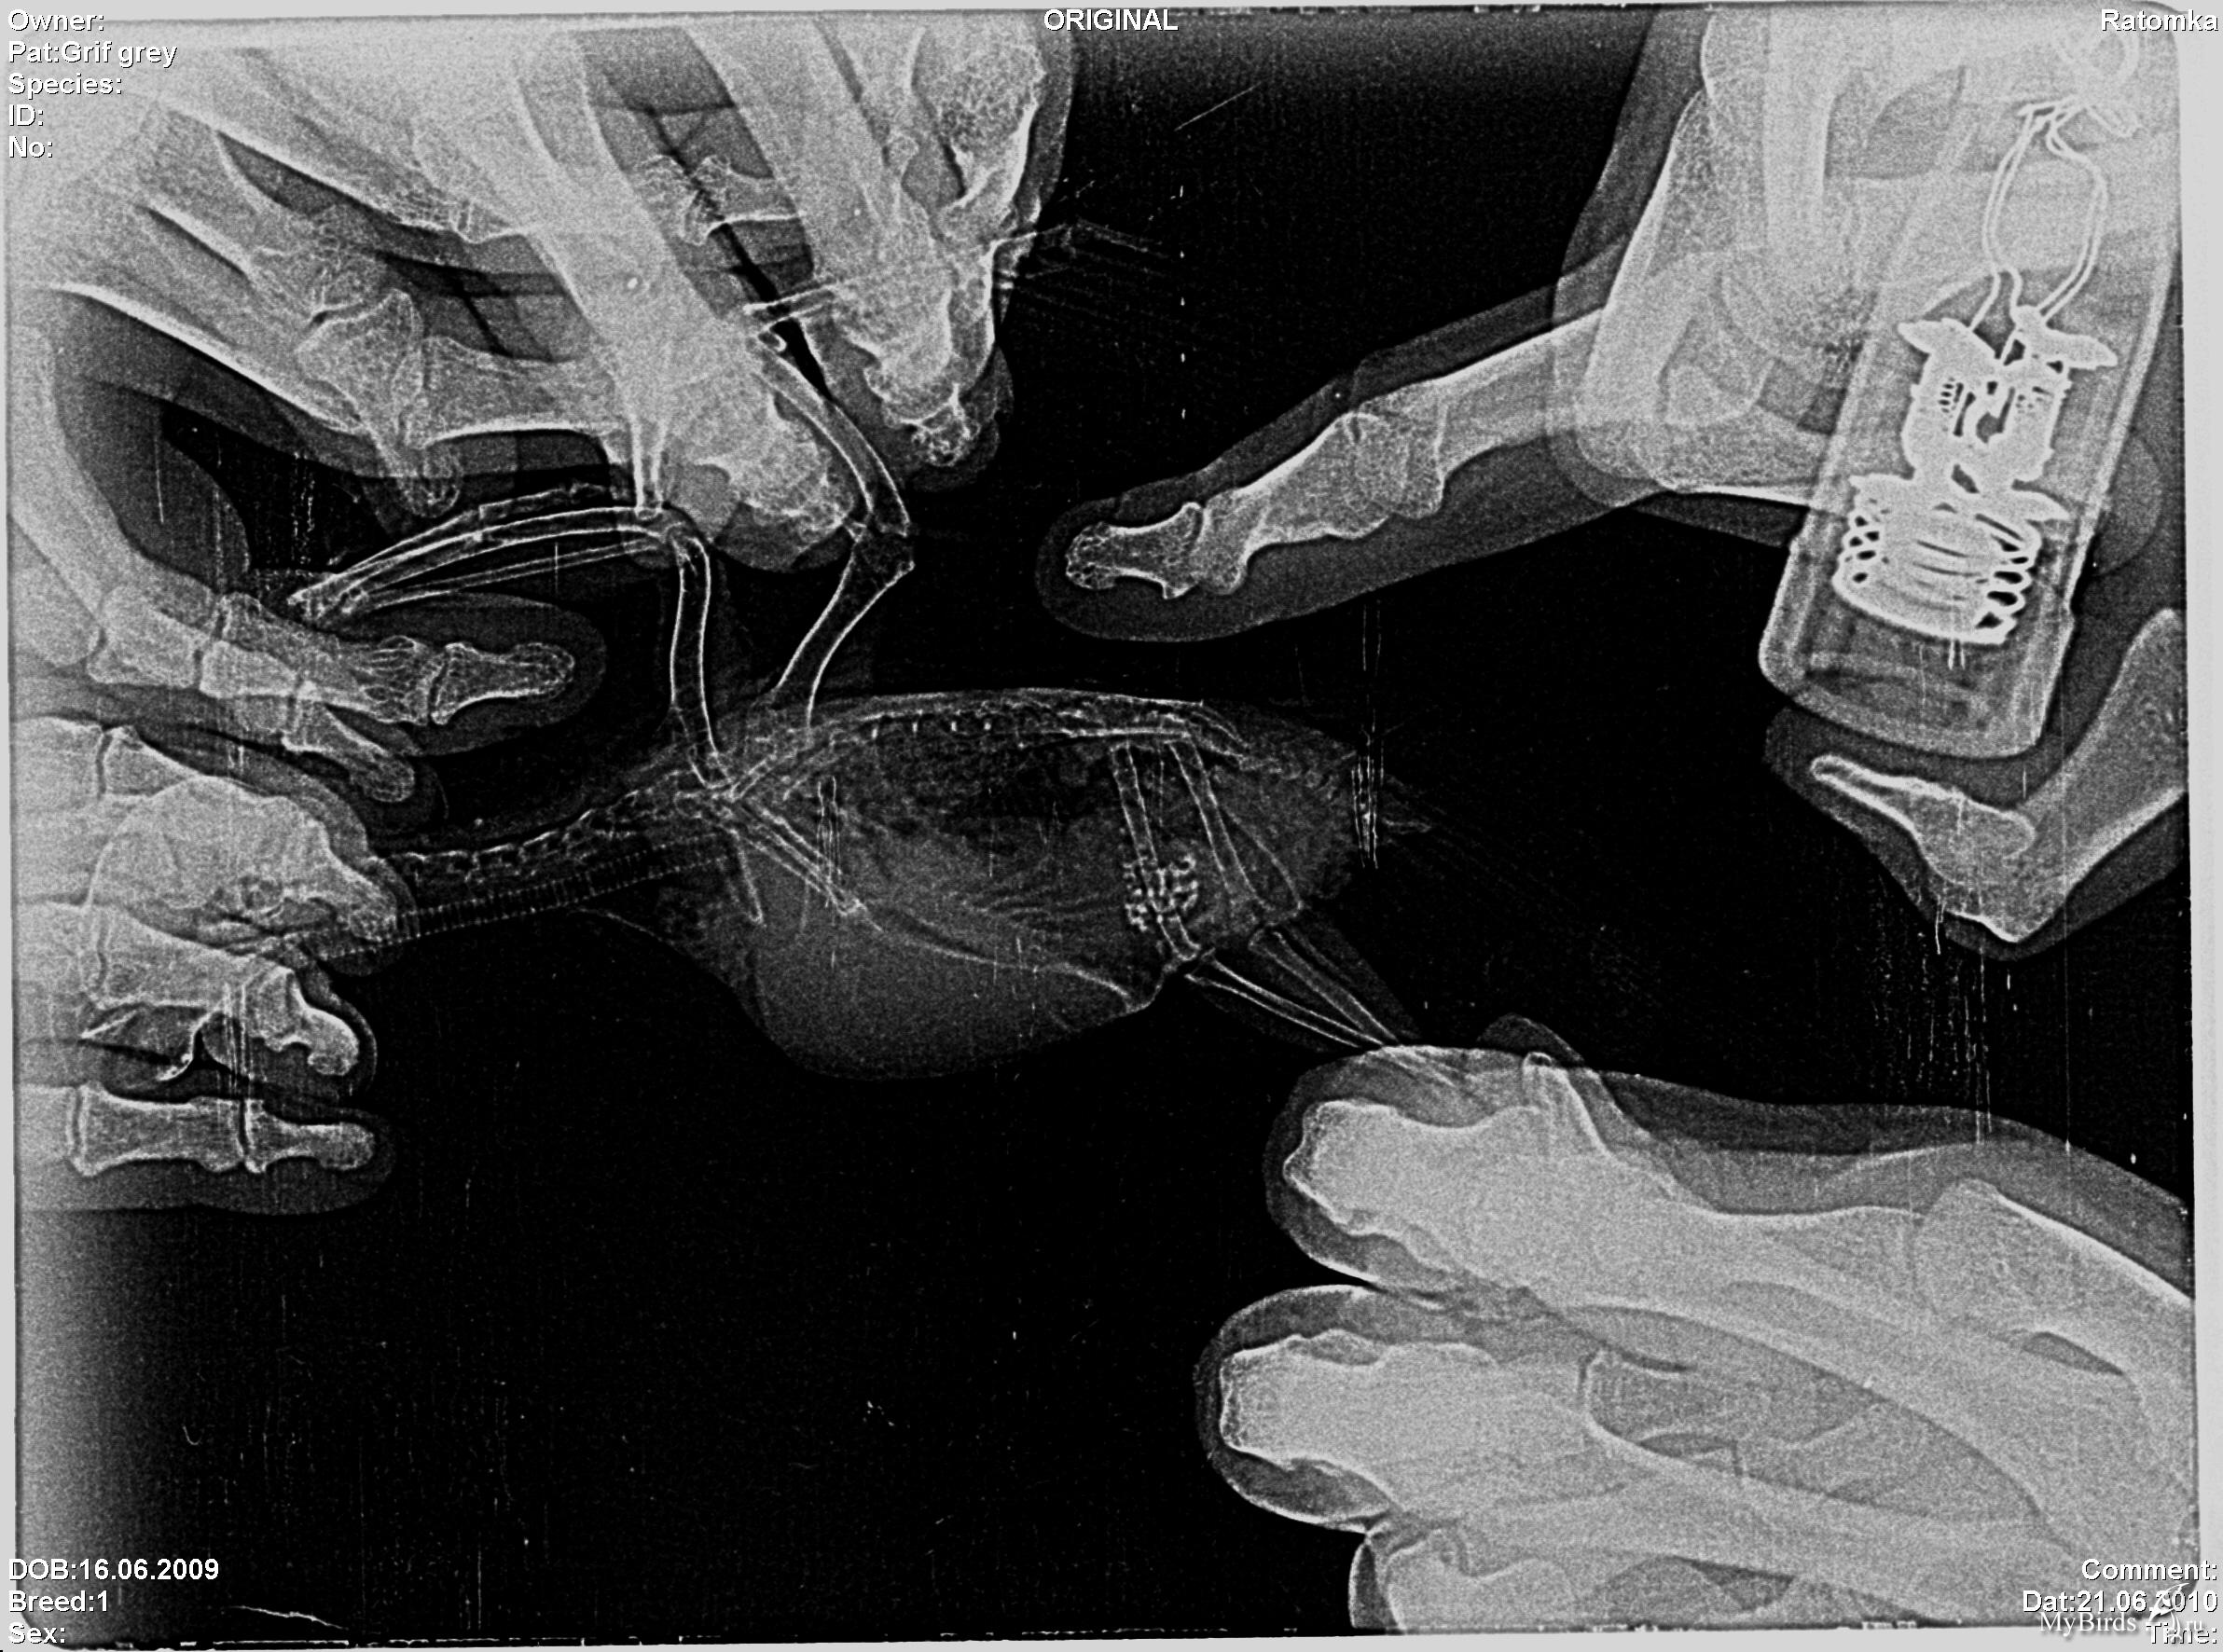

aleste Опубликовано 18 июля, 2010 Автор #84 Опубликовано 18 июля, 2010 С утра везем птичку на рентген, мне сказали что нужно сделать 2 проекции: дорсо-вентральная, птица на спине крылья раскрыты, и латеральная, птица на боку крылья отведены назад, ноги вытянуты вниз. С первой позой думаю справимся, а вот со второй ... даже незнаю как же ему отвести крылья назад, чтобы не дай бог не вывихнуть? Может Вы подскажете как птичку правильно держать во время рентгена. А может можно не отводить крылья назад? п.с. Как мне объяснили, снимки должны получиться примерно такими (это снимки не моей птички).

Cheshirski Опубликовано 19 июля, 2010 #85 Опубликовано 19 июля, 2010 А может можно не отводить крылья назад?905976[/snapback] Нет, мешать будут. Вообще, положение "крылья вверх" для птицы физиологично, и вроде еще не было случая, чтоб вывихнули или сломали.

aleste Опубликовано 19 июля, 2010 Автор #86 Опубликовано 19 июля, 2010 Рентген сделали. Врач, который делал рентген заметил, что недавно у попуая были сопельки и посоветовал обязательно сдать сопельки на бакпосев, (сопли были 15 июля, я об этом писал) а сегодня ноздри сухие, получится ли мазок из носа? Или делать его только в том случае, если сопли появятся снова? Получается нужно сделать два мазка: из зева и из носа?

Cheshirski Опубликовано 20 июля, 2010 #87 Опубликовано 20 июля, 2010 aleste, это фотоснимок неудачный, или сам рентген такой? Подробностей не видно, слишком контрастно... Получается нужно сделать два мазка: из зева и из носа?906490[/snapback] Достаточно будет из зева, там все соединяется. Проблема-то не в самом носу...